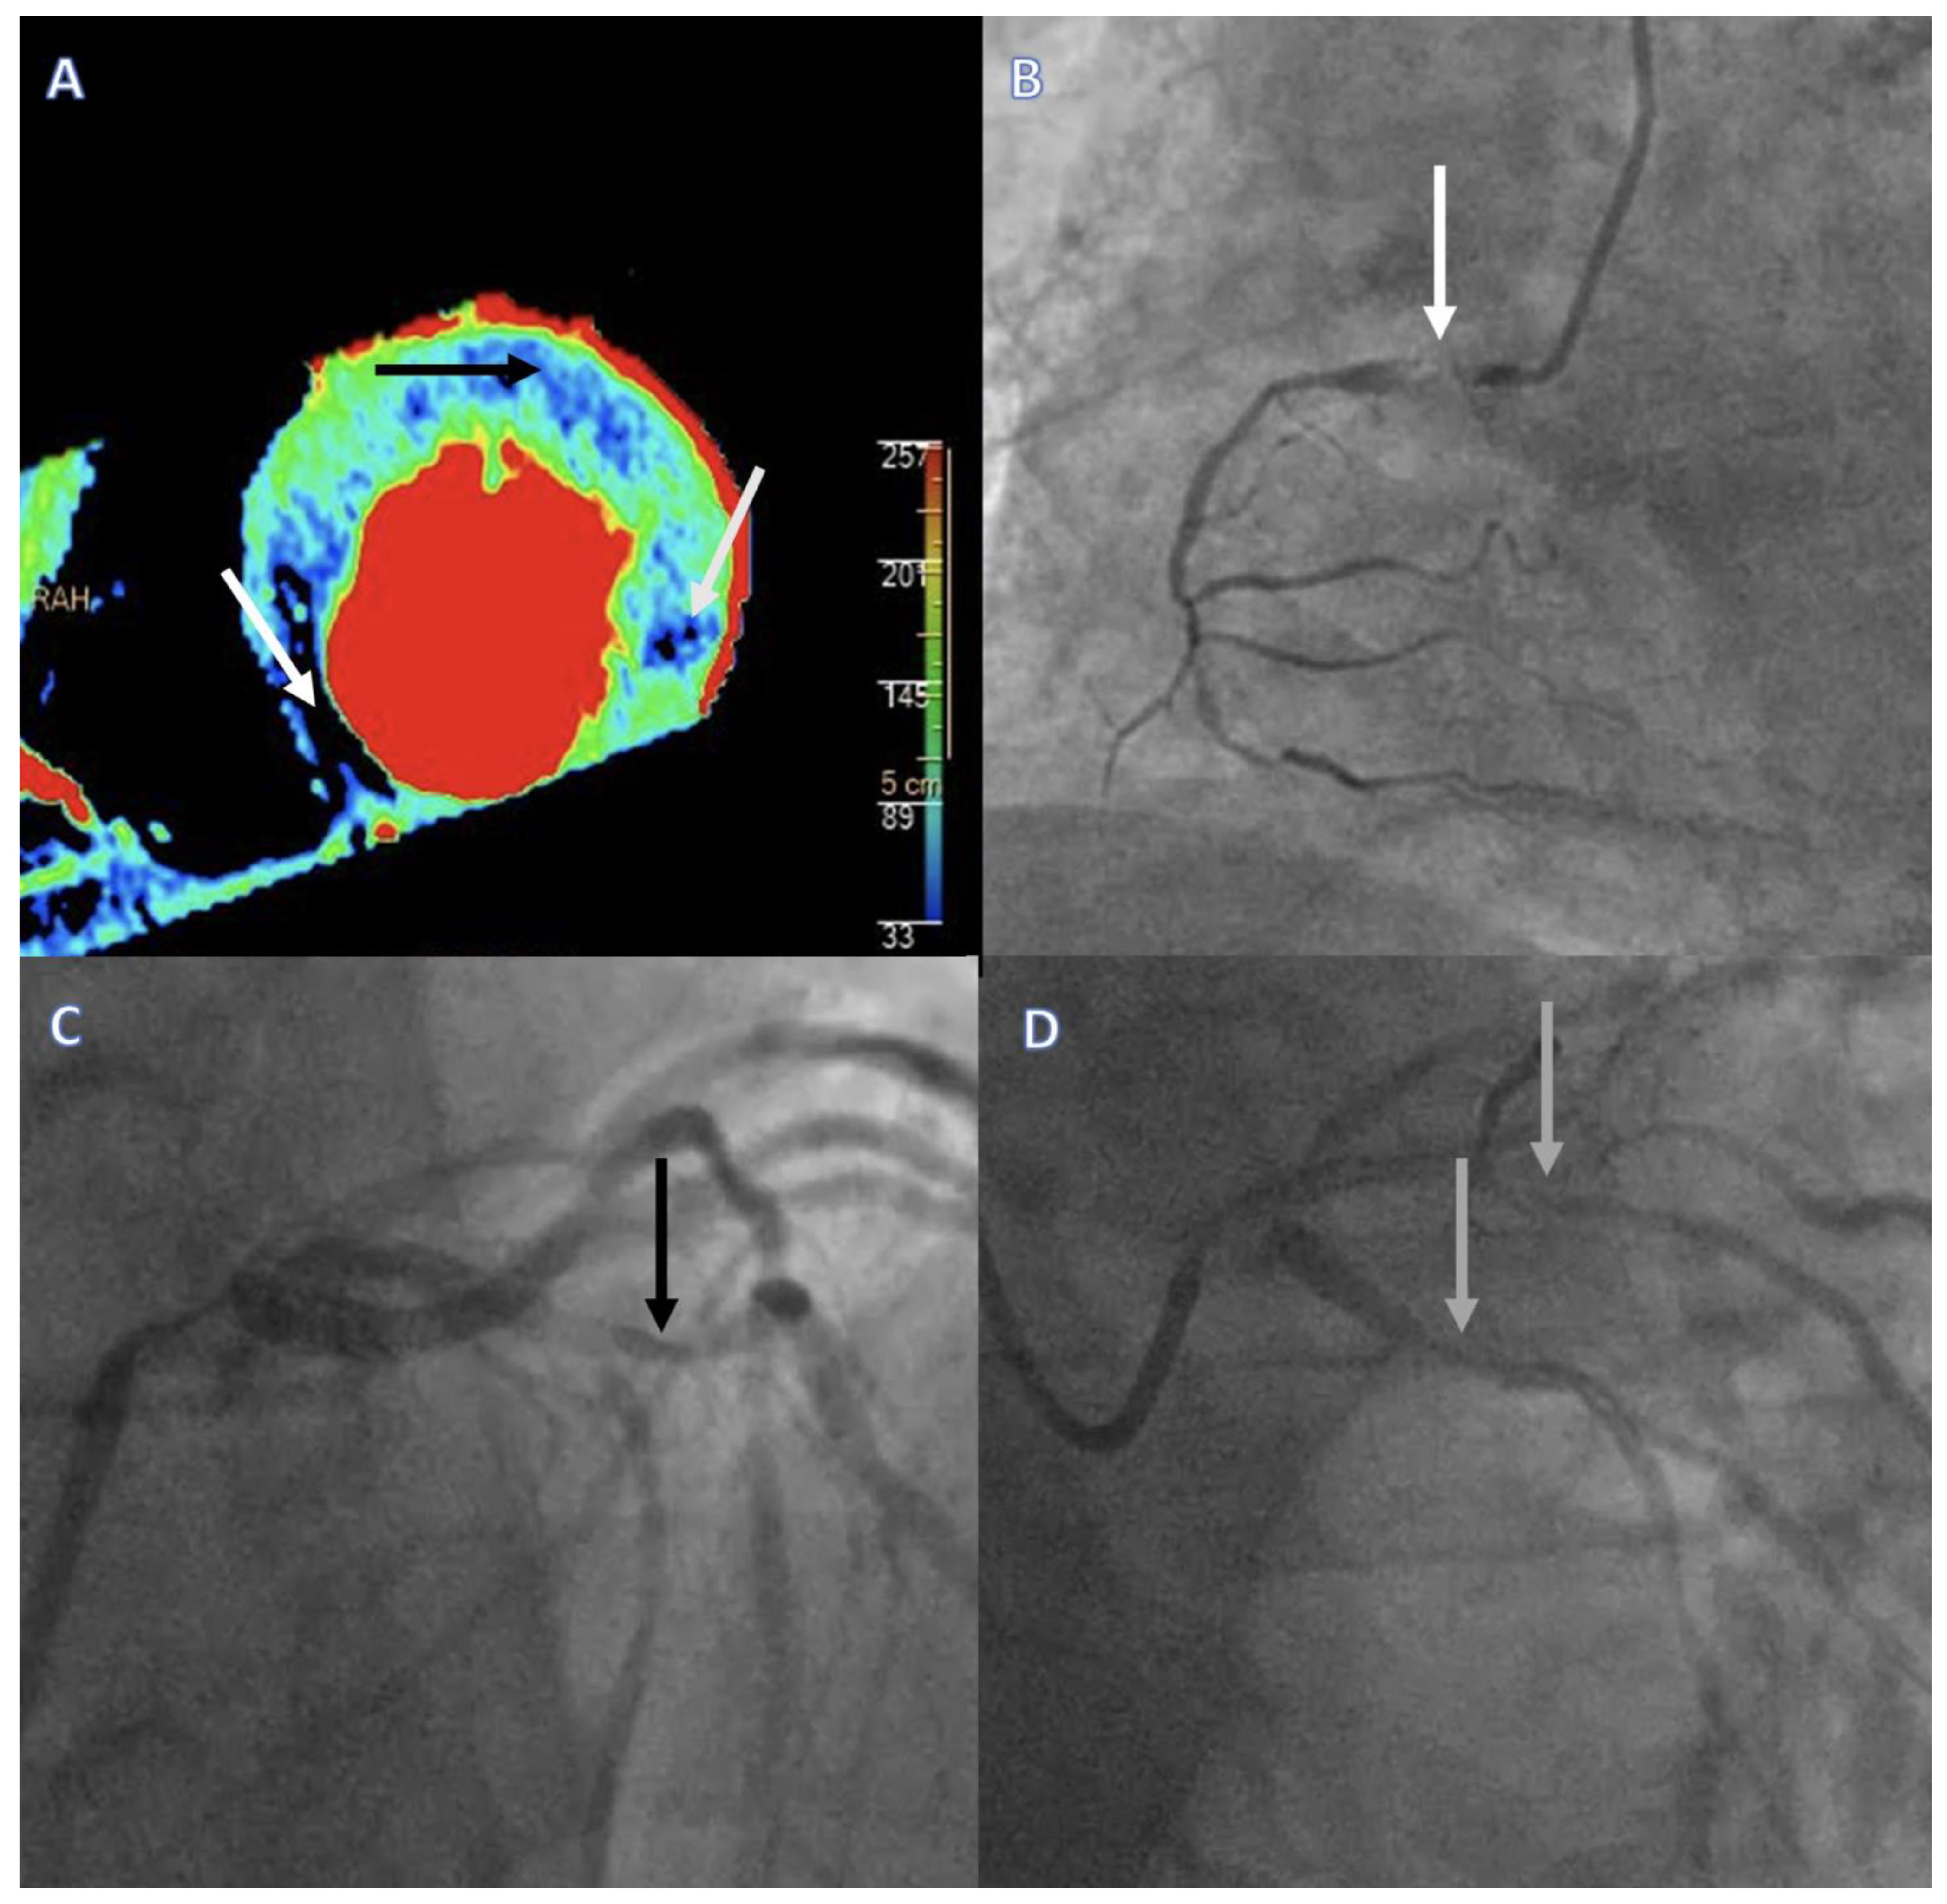

Figure 2. Regadenoson stress DPCT imaging results and corresponding invasive angiography and FFR findings in a multivessel CAD patient. (A) Regadenoson stress DPCT image depicting reduced myocardial blood flow (MBF < 101 mL/100 g/min) for all three main coronary territories. Necrosis was detected in the inferoseptal region (MBF 36 mL/100 g/min, white arrow), whereas ischemia was provoked in the anterior (MBF 69 mL/100 g/min, black arrow) and lateral (MBF 84 mL/100 g/min, gray arrow) wall of the LV. (BD) Corresponding invasive coronary angiography images verifying a chronic total occlusion of the right coronary artery (white arrow), severe stenosis of the left anterior descending artery (FFR = 0.65) (black arrow), and severe stenosis of the circumflex (FFR = 0.75) and intermediary coronary arteries (gray arrows). DPCT = dynamic perfusion computed tomography, FFR = fractional flow reserve, MBF = myocardial blood flow, LV = left ventricle.

The combination of anatomical and functional imaging by coronary CTA/regadenoson stress DPCT has several advantages in comparison to standard approaches to obstructive CAD screening in CLTI patients: (1) unnecessary invasive examinations in patients where peripheral access/re-access for catheterization is difficult may be avoided, and invasive coronary angiography could be restricted to patients where revascularization is probable [38]; (2) anatomical evaluation with pharmacological stress testing is ideal for detecting silent ischemia in the mobility-impaired CLTI population; and (3) DPCT utilizing absolute values of myocardial blood flow is more precise than SPECT relying on the differences between normal and ischemic myocardium and, thus, is better in the frequent setting of left main or multivessel disease in this patient population (Figure 2) [39] However, some limitations of this method must also be noted: (1) contraindication to regadenoson; (2) contraindication due to impaired renal function; and (3) contraindication due to poor general state and/or lack of cooperation, which are also more frequent in the CLTI patient population.